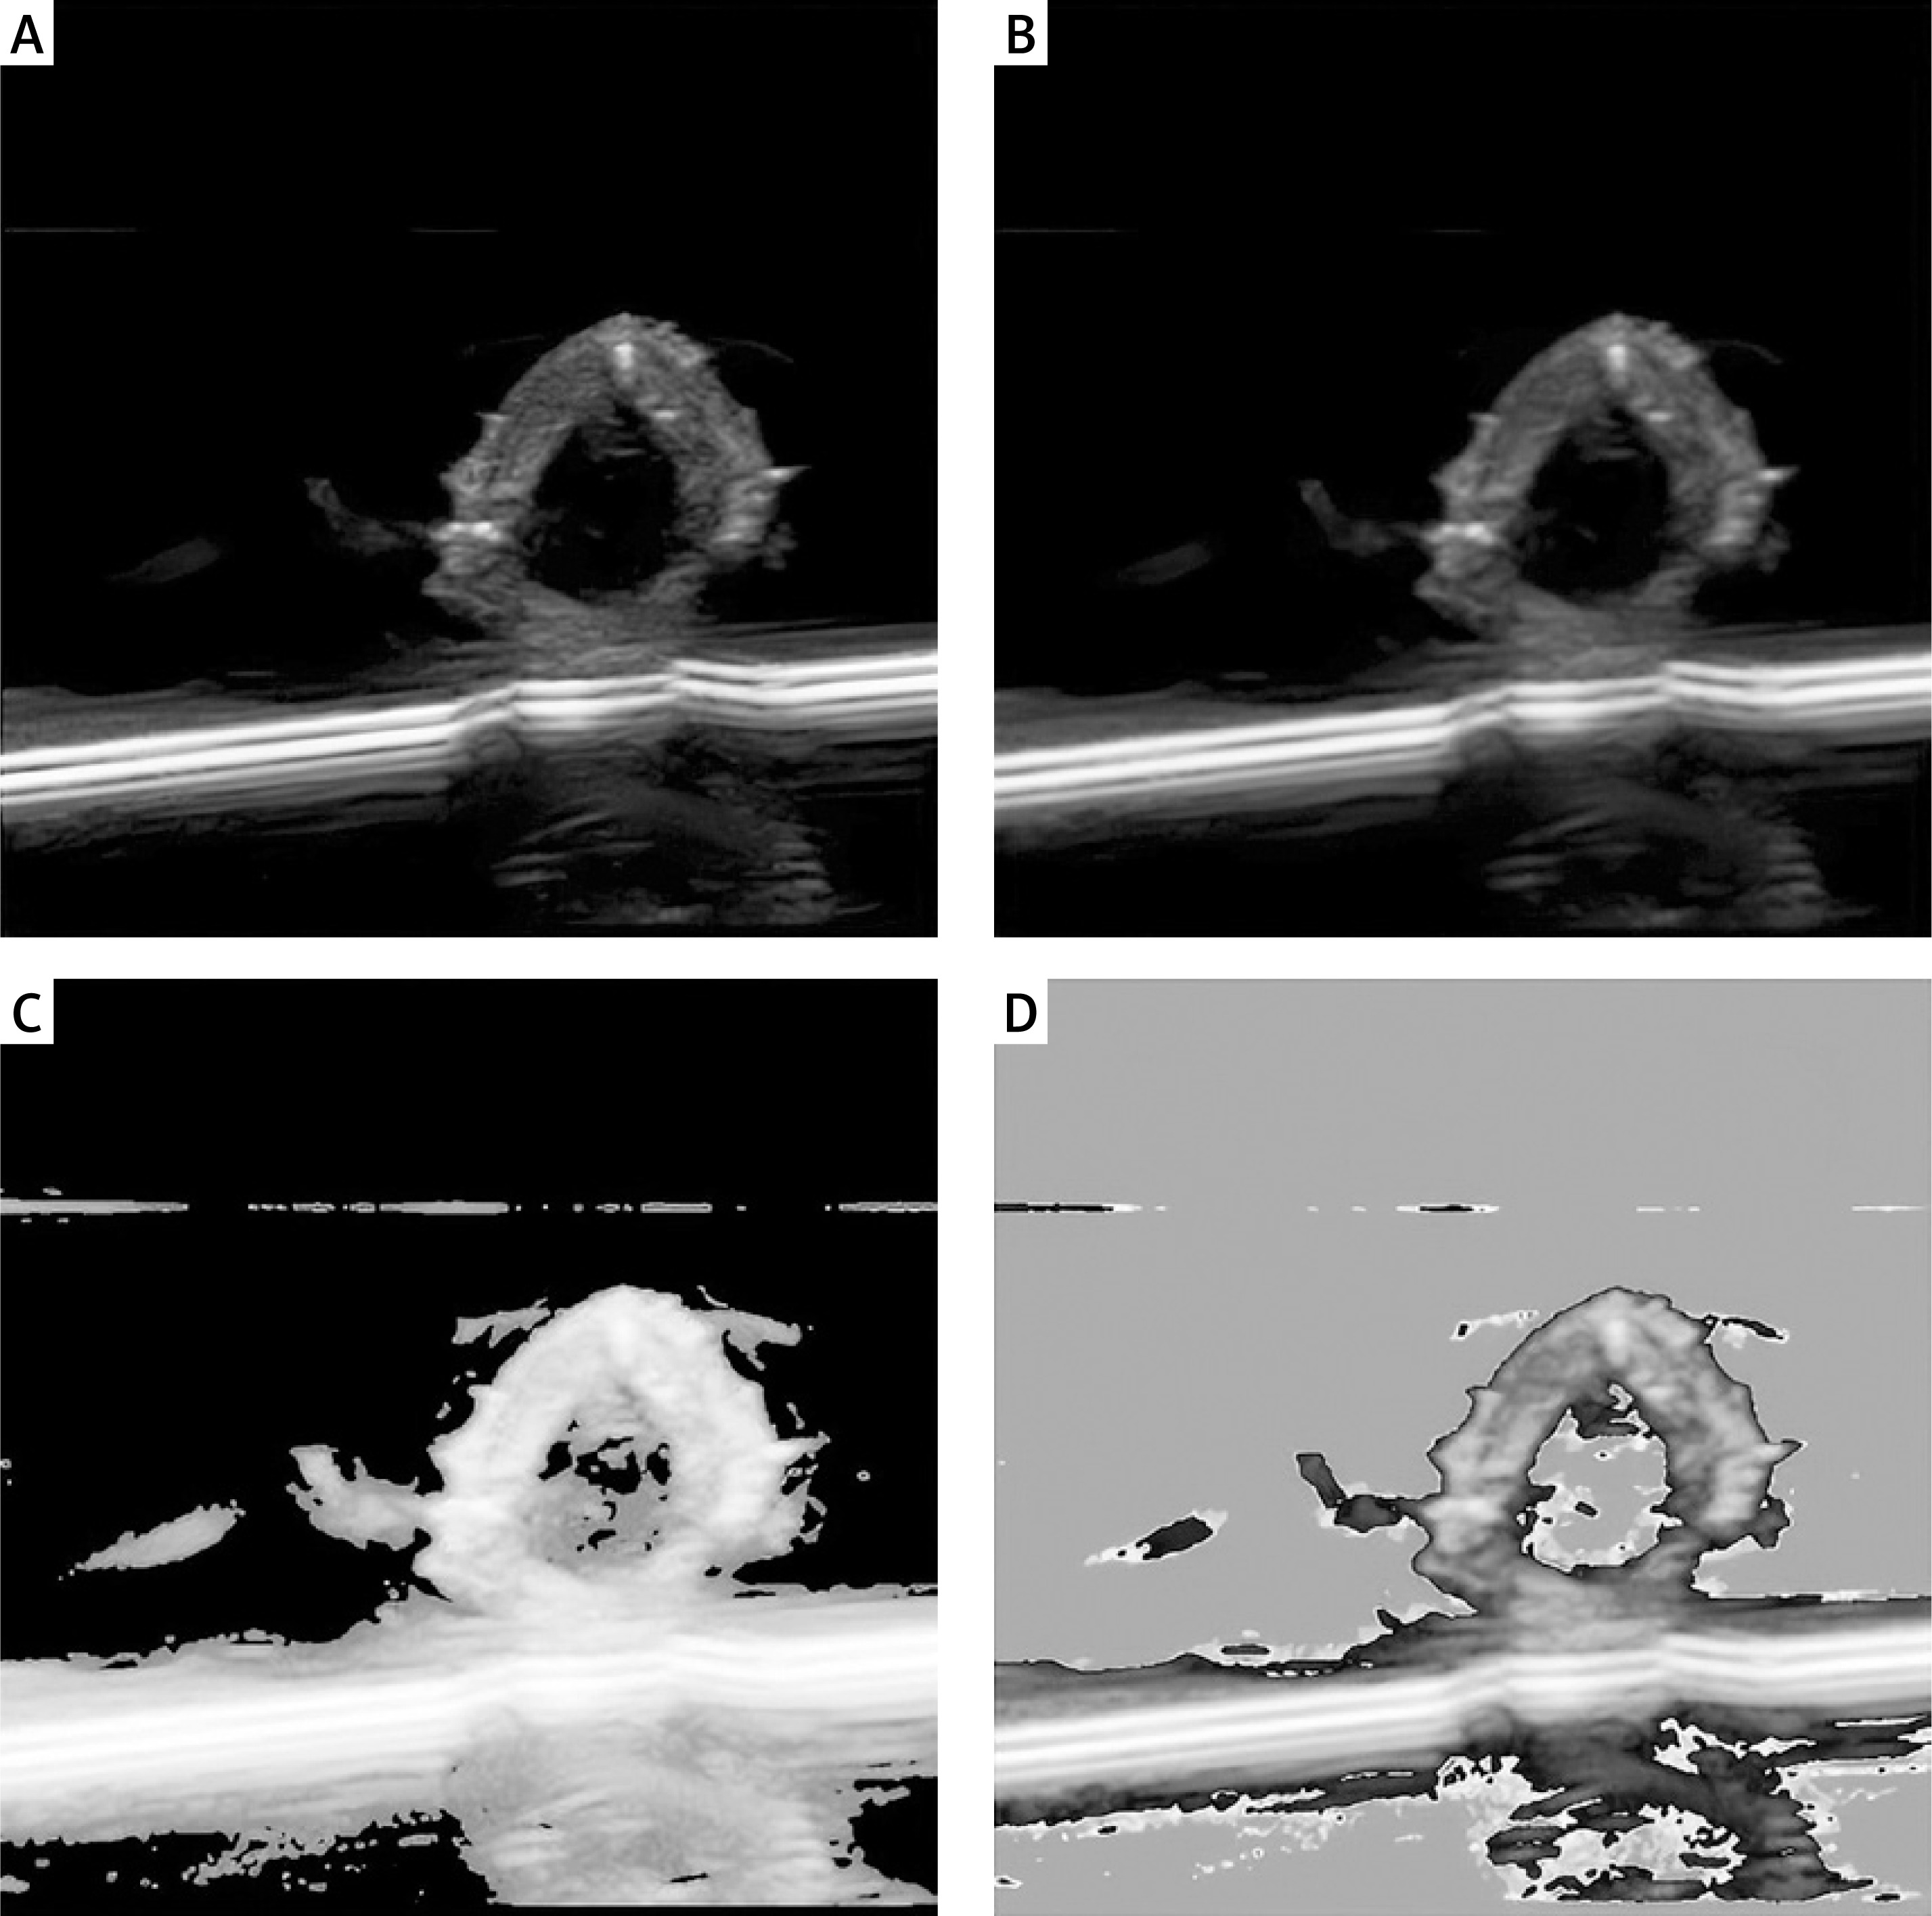

To enhance data quality, images that were blurry, low-resolution, or lacked critical information were excluded. Furthermore, all images were resampled to a standardized resolution to ensure consistency across the dataset. Initial denoising and contrast enhancement were performed to meet the requirements of subsequent DL model training (Supplementary Figure S1).

Image preprocessing and annotation

During the preprocessing phase, various data augmentation techniques – including random rotation, scaling, and cropping – were applied to enhance image quality and improve the model’s generalizability across different scenarios. Image pixel values were normalized using a standardization method to ensure consistency in feature distribution. Annotation was performed collaboratively by multiple experienced radiologists, who focused on marking atherosclerotic plaque lesions, categorizing lesion types, and documenting distribution characteristics. A semi-automated segmentation tool based on a DL model assisted the experts in improving both efficiency and annotation quality. The annotated data were subjected to cross-validation to ensure the accuracy of lesion boundaries and features (Supplementary Figure S2).